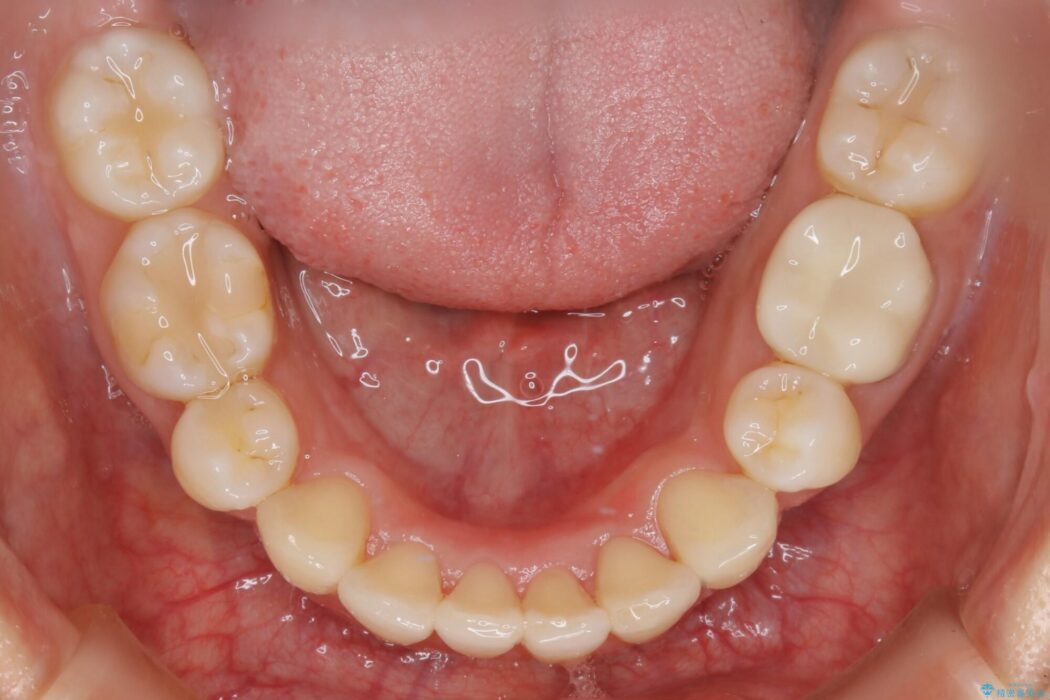

笑った時に見えるガタついていた見栄えが改善されて歯列弓もきれいな形に整い、患者様にはご満足いただけました。